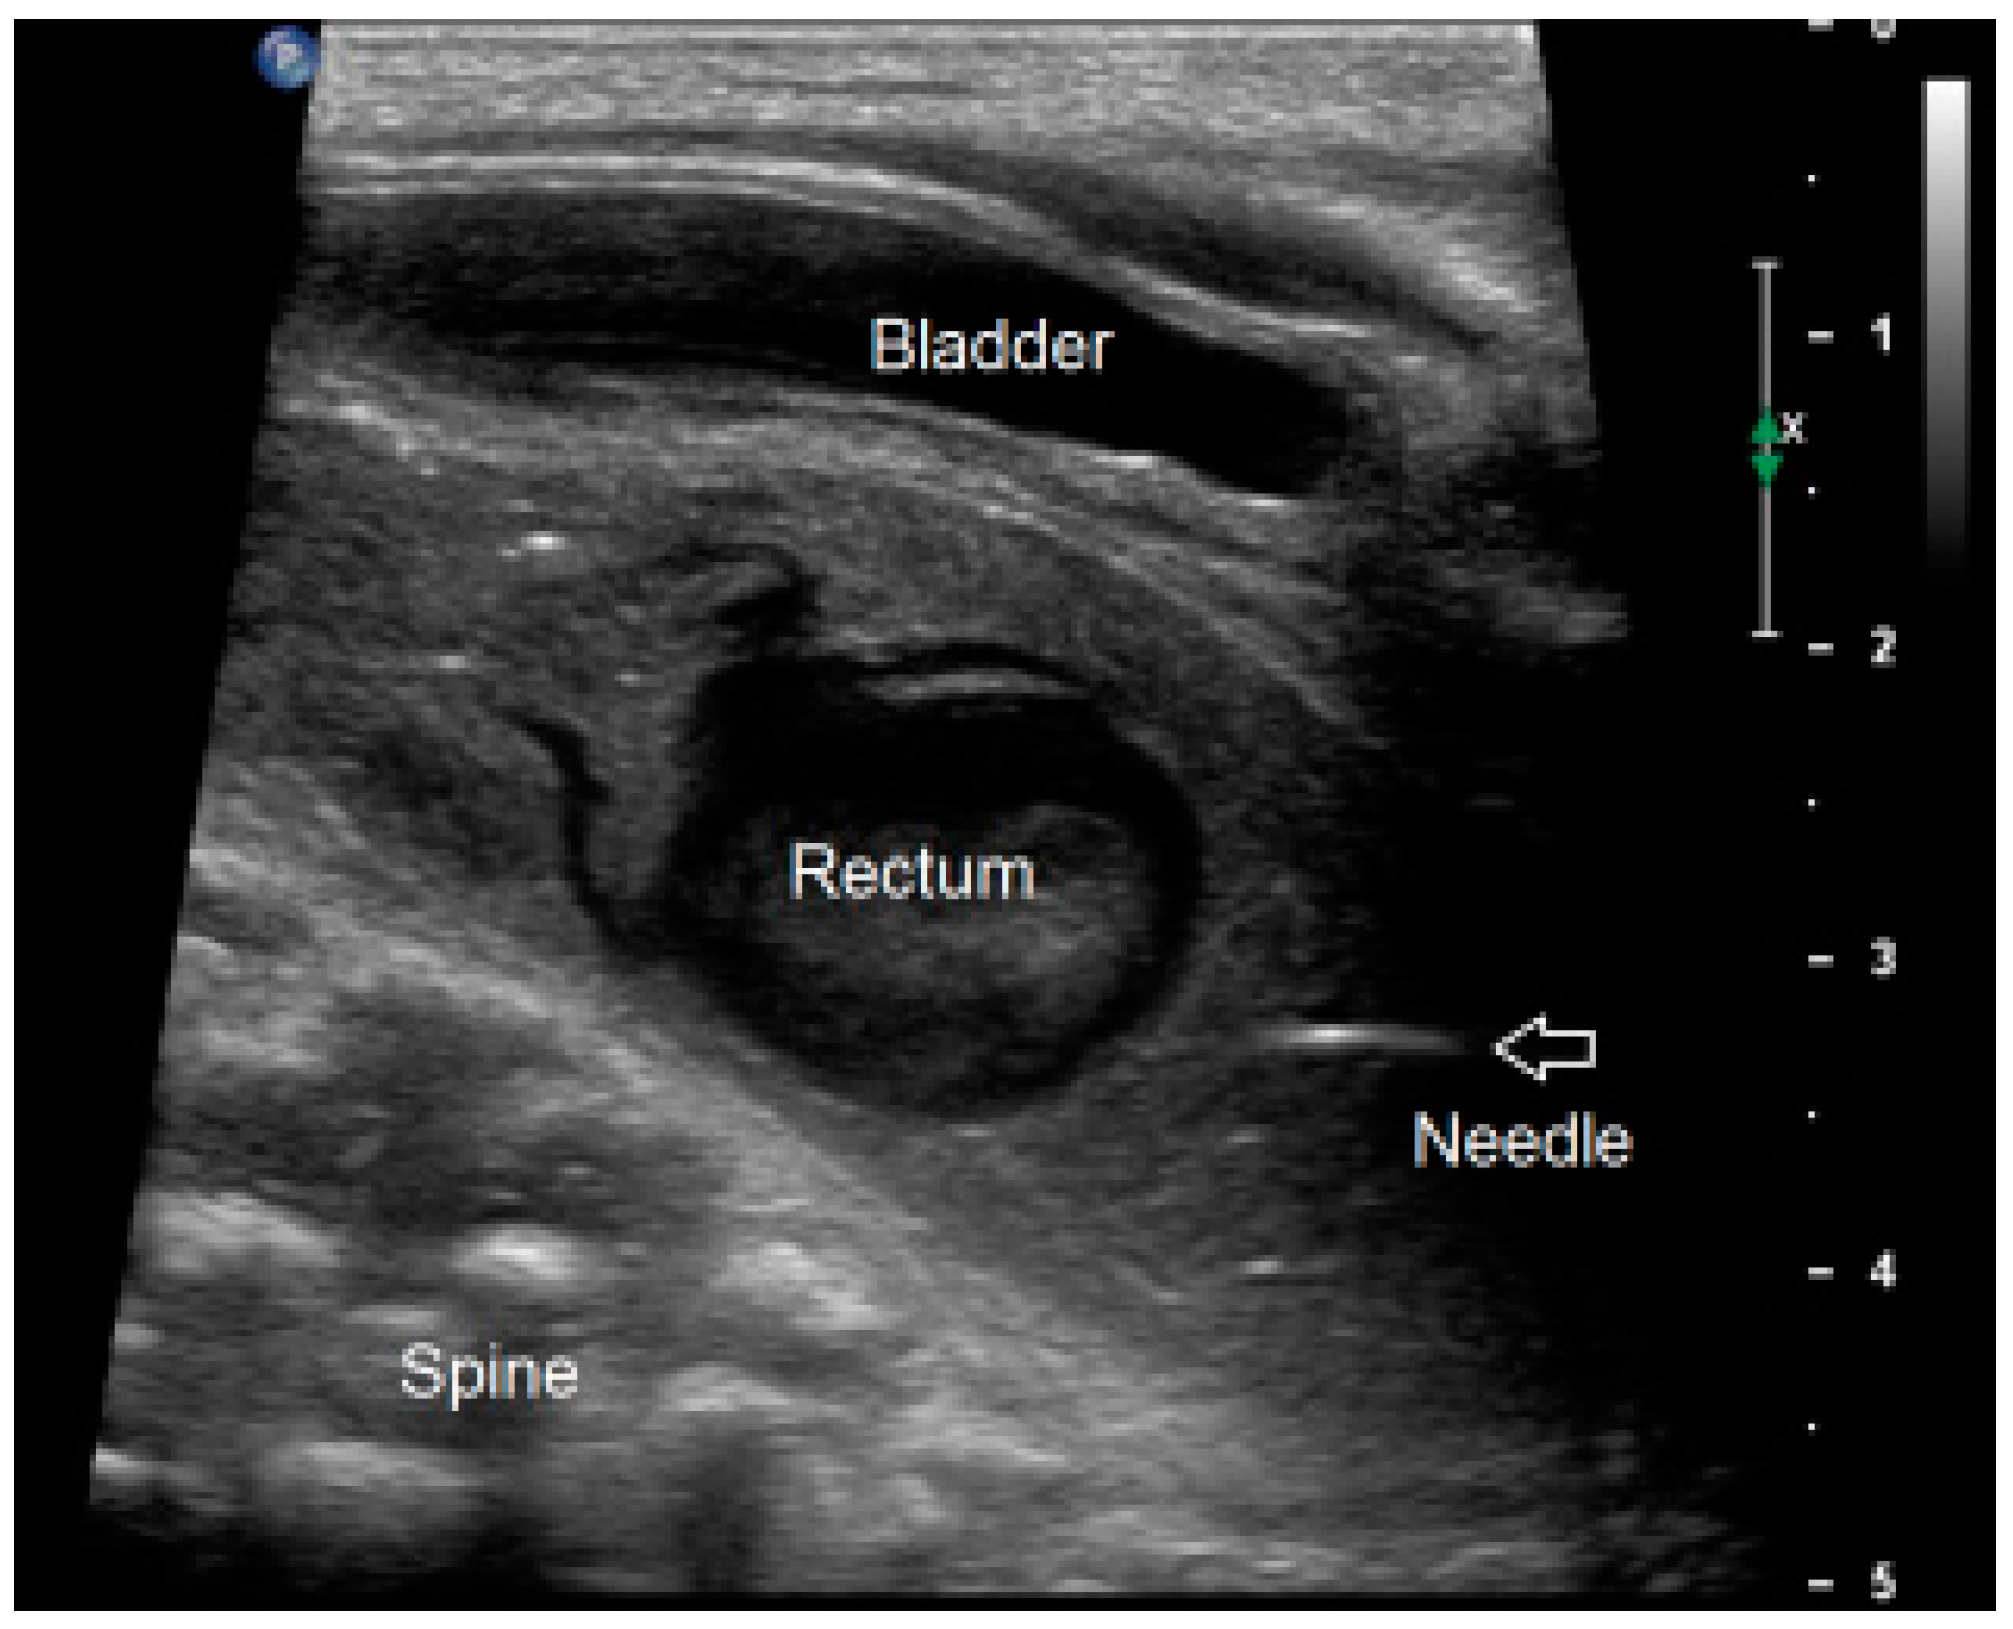

2.3.2. Ultrasound-Guided PARP (uPARP)